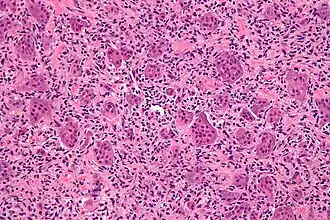

![]() Микрофотография гигантских клеток остеобластокластомы кости, характерно выделяются гигантские клетки. Окрашено гематоксилином и эозином. | |

Микроскопическая структура гигантоклеточной опухоли кости, в основном, представлена двумя типами клеток. Преобладающее большинство клеточных элементов составляют веретенообразные, овальные и округлые клетки с умеренно выраженной цитоплазмой и светлым ядром, содержащим небольшое количество хроматина. В ядрах определяются одно, а иногда два хорошо различимых ядрышка, могут выявляться фигуры митоза, как правило, типичные.

Другим клеточным компонентом являются многоядерные гигантские клетки. Эти клетки очень похожи на нормальные остеокласты, но обычно несколько крупнее их и имеют закругленный контур. Они содержат 20-30 и более ядер, большинство из которых располагаются в центре клетки. Ядра многоядерных клеток обычно лежат изолировано друг от друга и, практически, не отличаются от ядер одноядерных клеточных элементов. Цитоплазма этих клеток слегка базофильна. В многоядерных гигантских клетках фигур митоза не определяется. Эти клетки равномерно (важный дифференциальный диагностический признак!) расположены в опухоли.